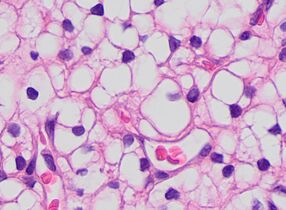

The most commonly used stain in histology is a combination of hematoxylin and eosin (often abbreviated H&E). Hematoxylin is used to stain nuclei blue, while eosin stains the cytoplasm and the extracellular connective tissue matrix of most cells pink. There are hundreds of various other techniques which have been used to selectively stain cells. Other compounds used to color tissue sections include safranin, Oil Red O, congo red, silver salts and artificial dyes. Histochemistry refers to the science of using chemical reactions between laboratory chemicals and components within tissue. A commonly performed histochemical technique is the Perls' Prussian blue reaction, used to demonstrate iron deposits in diseases like Hemochromatosis.[2]

Recently, antibodies have been used to stain particular proteins, lipids and carbohydrates. Called immunohistochemistry, this technique has greatly increased the ability to specifically identify categories of cells under a microscope. Other advanced techniques include in situ hybridization to identify specific DNA or RNA molecules. These antibody staining methods often require the use of frozen section histology. These procedures above are also carried out in the laboratory under scrutiny and precision by a trained specialist medical laboratory scientist (a histoscientist). Digital cameras are increasingly used to capture histopathological images.